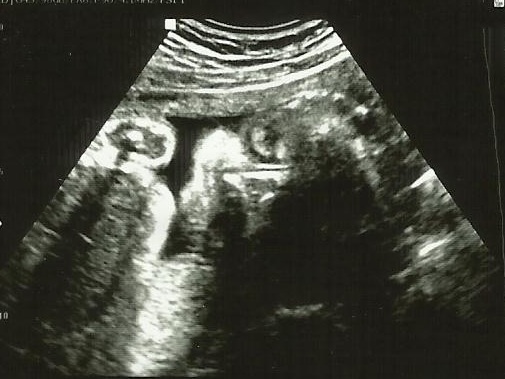

Ahoj děvčata, tak se hlásím po dnešní kontrole. Eli je konečně otočená hlavičkou dolů a paní doktorka říkala, že by to ta už mělo zůstat, tak snad už nebude moc cestovat. Jinak má už 1130g říkala teda, že je to dobrý, ale není to žádnej obřík, na míru jsme se zapomněla zeptat. Ale malá je v pořádku a to je hlavní. Říkala jsem jí o tuhnutí břicha a říkala, že pokud to mám 5x nebo 10x za den, tak se tím nemám vůbec znepokojovat, že to je normální jak se zvětšuje děloha, že to teď budu pociťovat. Tak jsem jí jen řekla,že když se to horší,že si beru hořčík, tak říkala, že v pohodě, ale že to je takhle v normě. Kontrolovala mi pro jistotu i čípek a prý 43mm, takže je dost dlouhej a pevnej, tak snad hezky vše tak bude pokračovat až do května......No jen ta cukrovka, představte si, že mám první i druhou hodnotu dobrou a třetí mám o 0,2 vyšší nad normu a už musím držet dietu. Takže žádné sladké a i pozor na ovoce a přílohy a tak....No ještě, že je to jen na 3 měsíce.

Přidávám foto z dnešního UZ...vypadá to jako by měla oteklá očička a nosánek protáhlej až k pusince :-) Ale rozkošně se usmívá